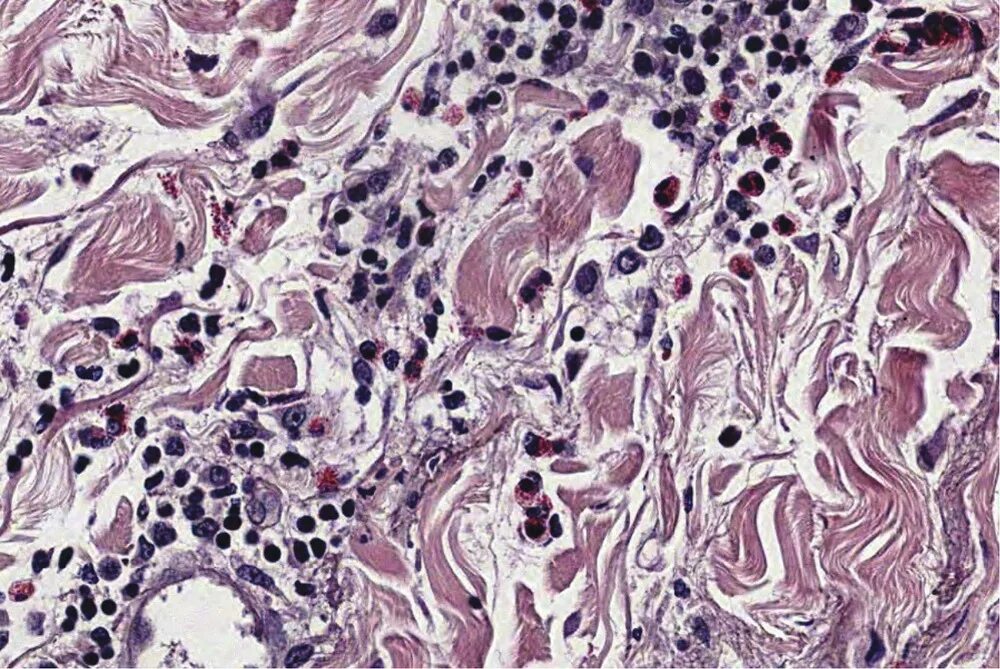

Смешанный периваскулярный инфильтрат при крапивнице